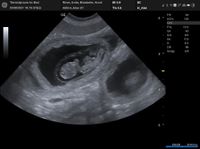

FANNY & MIKA sind stolze Eltern von 5 Puppies geworden.

VIGGO, VALETTA, VENIA, VIKA & VINNY

...und alle sind gesund.

KNÖDI & MIKA ERWARTEN NACHWUCHS...ENDE DEZEMBER 2023